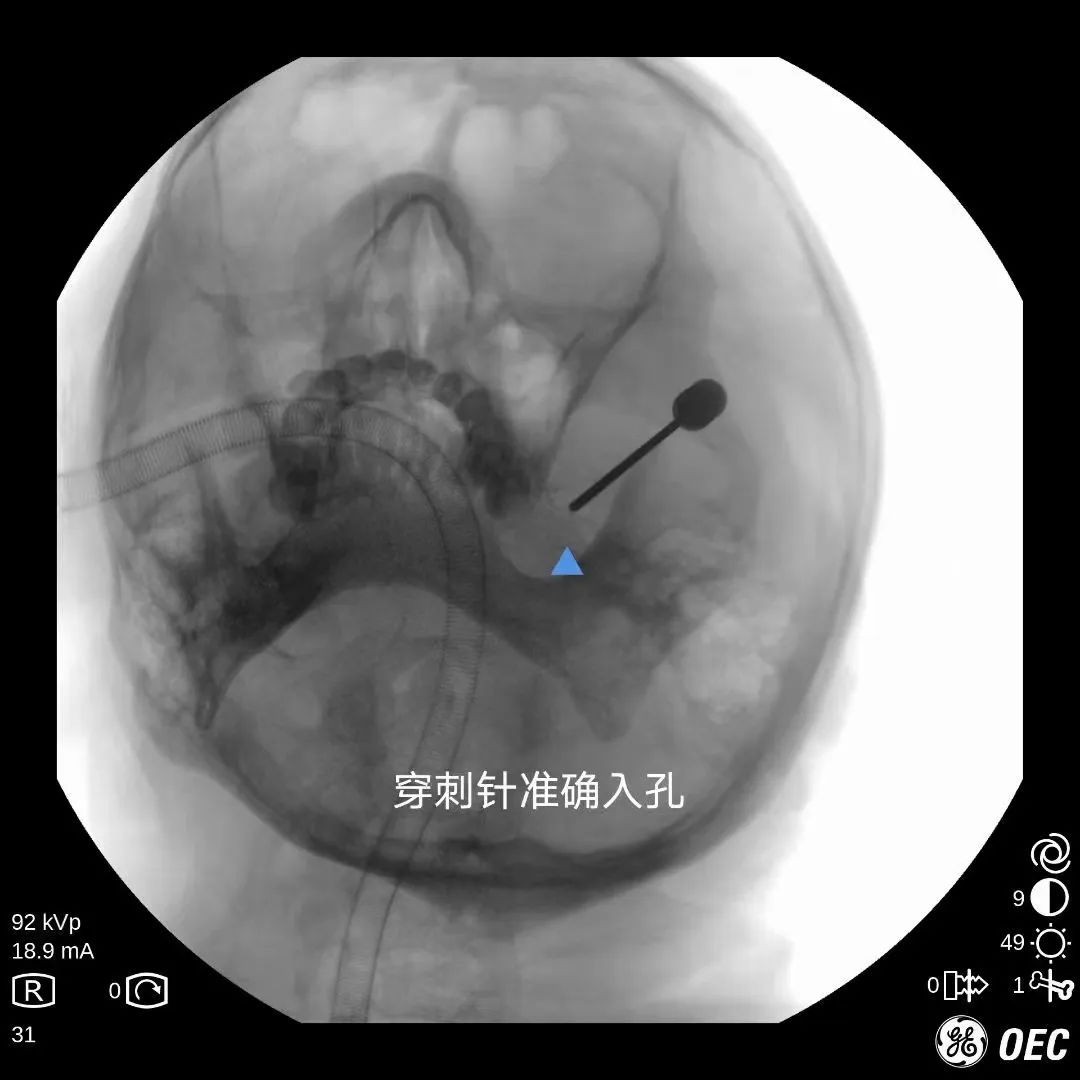

经皮穿刺三叉神经半月节球囊压迫术 :手术在C型臂及超声引导下成功穿刺至颅底孔隙,利用球囊的压力对三叉神经的关键部位进行压力治疗,使痛觉信号无法上传到大脑从而达到止痛的目的。

这种手术方法 无手术切口、安全有效、并发症少、患者恢复快, 迅速得到业界追捧,但因对术者技巧、手术器械、手术设备要求较高,开展起来有一定难度。